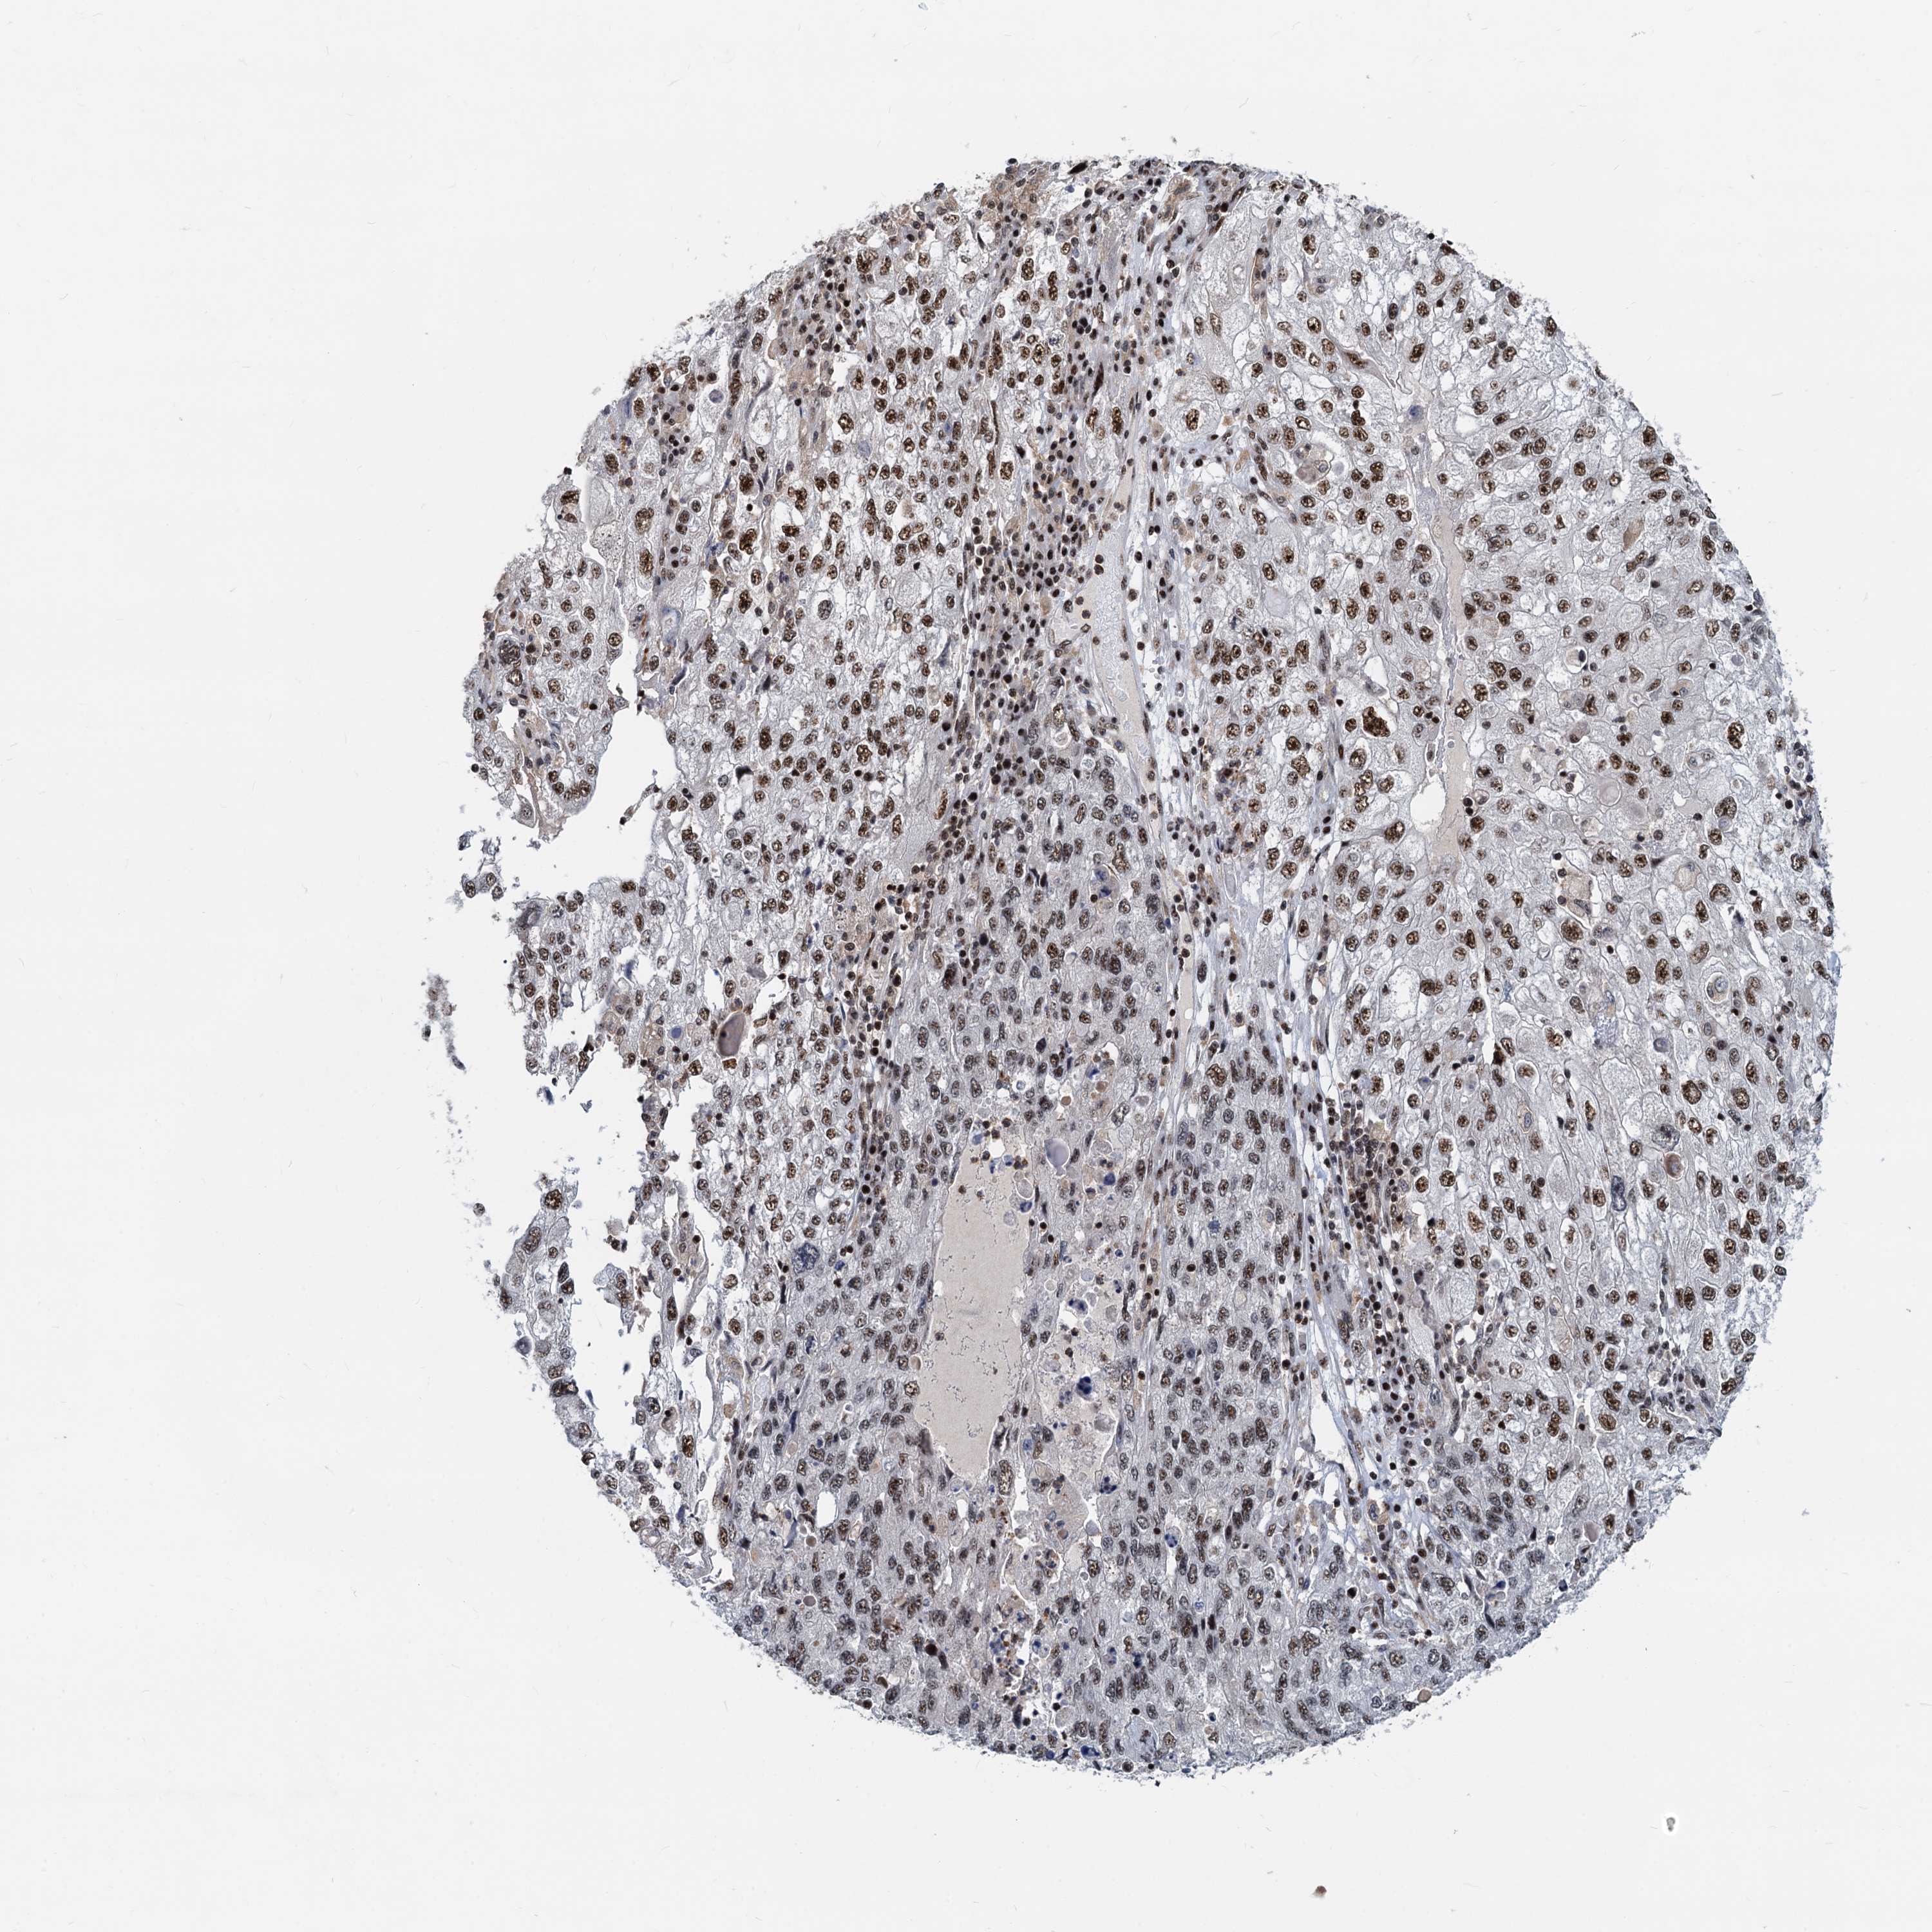

ENDOMETRIAL CANCER - Protein expressioni

A mouse-over function shows sample information and annotation data. Click on an image to view it in a full screen mode. Samples can be filtered based on level of antibody staining by selecting one or several of the following categories: high, medium, low and not detected. The assay and annotation is described here.

Note that samples used for immunohistochemistry by the Human Protein Atlas do not correspond to samples in the TCGA dataset.

Antibody stainingi

Antibody staining in the annotated cell types in the current human tissue is reported as not detected, low, medium, or high, based on conventional immunohistochemistry profiling in selected tissues. This score is based on the combination of the staining intensity and fraction of stained cells.

Each image is clickable and will lead to virtual microscopy that enables deeper exploration of all samples and also displays staining intensity scores, fraction scores and subcellular localization as well as patient and tissue information for each sample.

Antibody HPA040252

Staining

High

Medium

Low

Not detected

Intensity

Strong

Moderate

Weak

Negative

Quantity

>75%

75%-25%

<25%

None

Location

Nuclear

Cytoplasmic/membranous

Cytoplasmic/membranous,nuclear

Adenocarcinoma, NOS

Adenocarcinoma, metastatic, NOS